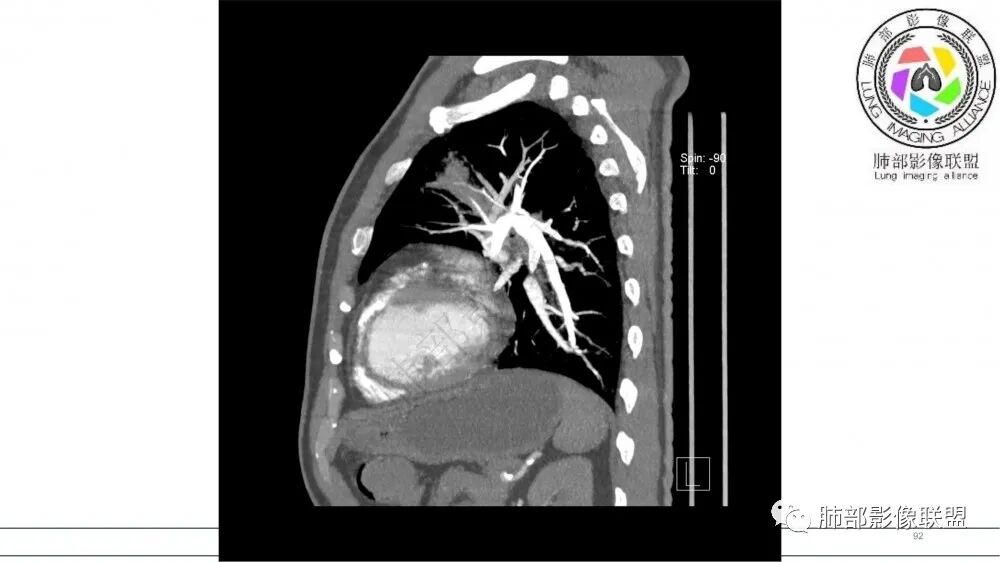

左肺上叶尖后段支气管近端截断,远端见高密度铸型,远侧见阻塞性改变,老年男性,吸烟史,考虑恶性,鳞癌。ABPA代排

老年男性,长期吸烟史。左上肺前段沿支气管走形的指套样病变,增强可见病灶强化(排除结核、ABPA(也无气喘症状)),远端多发点状高密度影。考虑恶性肿瘤,鳞癌可能性大。

指套征,扩张支气管内软组织强化,远侧肺野阻塞性炎,纵隔、左肺门肿大淋巴结;老年男性,吸烟,考虑鳞癌,鉴别小

2021年8月6日晨读病例结果:小细胞肺癌

指套征:是影像征象,胸部平片表现为手指状密度增高影,以肺门为中心呈放射状分布,CT显示扩张支气管内低密度黏液栓形成或实性病变,呈管状、树枝状或卵圆形密度增高影;支气管扩张伴近端梗阻时,扩张支气管内部黏液分泌物不能排出而形成。可以伴随远端空气潴留征、阻塞性炎症。

研究报道,中心型 SCLC 经 CT 扫描后通常支气管表现为鼠尾样狭窄,肺门或纵隔肿块明显,由于肿块沿管壁生长表现为顺延支气管形态的不规则形状。病灶相对特征性影像学表现比如鸭蹼状、腊肠状、葫芦状及葡萄状改变,可以出现血管包埋,很少有空洞、空泡,较少引发肺不张,阻塞性炎症成都较轻。与一般肺癌比较,恶性程度高,侵袭力强、病灶很小就容易远处转移!Herzberg 等[19]研究指出,20%以上 SCLC 倍增时间短,预后不良。